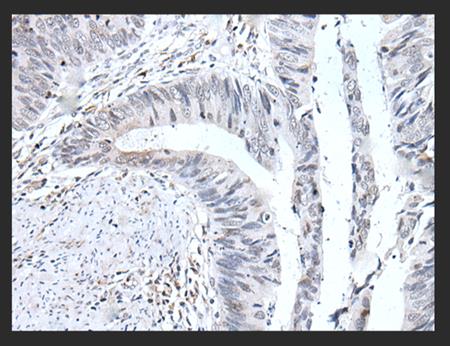

图1 UBE2T抗体显微图

在分子生物学和癌症研究实验室中,UBE2T抗体是不可或缺的工具。如UBE2T抗体用于检测不同细胞系或组织样本中UBE2T蛋白的表达水平,比较癌组织与正常组织的差异。用于在肿瘤组织切片上定位UBE2T蛋白,观察其在细胞内的分布(通常在细胞核和细胞质中),并通过对染色强度的评分来评估UBE2T的表达与临床病理参数(如分期、分级、生存率)的关系。利用UBE2T抗体抗体将UBE2T蛋白及其相互作用蛋白复合物从细胞裂解液中“拉”下来,用于寻找UBE2T的E3连接酶伙伴或其底物蛋白等。